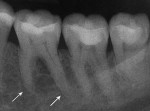

Five cases met the criteria as set forth in the study and are summarized in Table 1; radiographs of the five cases are shown in Figure 1 through Figure 21. Ages ranged from 15 to 48 years. Four patients were male and one female. All five cases involved Caucasian patients. Two cases involved the distal roots of mandibular first molars bilaterally (Figure 1, Figure 2, Figure 3, Figure 4, Figure 5, Figure 6, Figure 7, Figure 8, and Figure 18, Figure 19, Figure 20, and Figure 21); one case involved both roots of the mandibular first molars bilaterally (Figure 11, Figure 12, Figure 13, Figure 14); and two cases involved the mandibular second premolar unilaterally (Figure 9 and Figure 10, and Figure 15, Figure 16, and Figure 17). Two of the patients presented with symptoms similar to cracked-tooth syndrome (Table 1, Case 3 and Case 4), one with “chronic reversible pulpitis” (Table 1, Case 1), and two were asymptomatic (Table 1, Case 2 and Case 5).

Patients in all five cases exhibited PARR of the involved roots, as previously described (Figure 1 through Figure 21).40 The roots showed shortening and blunting of the apex of greater than 2 mm in all five cases. In three of the five cases, the PARR self-arrested without any treatment. The mandibular left first molar in Case 1 (Figure 5, Figure 6, Figure 7, and Figure 8) received conventional root canal therapy (RCT), while the mandibular right first molar in Case 3 (Figure 11, Figure 12, Figure 13, Figure 14) received a bonded ceramic crown. The PARR appears to have arrested in these two cases, and the outcome of the treatment in relation to the resorption could not be determined. The symptoms the patients were experiencing did eventually resolve. Consequently, all five study cases became symptom-free, including the patient who received conventional RCT (Case 1).

LIAR primarily occurs in the mandibular first molars and mandibular premolars, sometimes bilaterally. In two cases, LIAR occurred in the second premolars unilaterally while the other three cases involved the mandibular first molars, bilaterally. Cases 1 and 5 involved the distal root of the mandibular first molars bilaterally, while Case 3 involved both mesial and distal roots bilaterally.

LIAR has been reported as an asymptomatic process identified by routine radiographs. However, in three of the five cases in the present study, the teeth were symptomatic, with two cases being asymptomatic and discovered on routine radiographs. Two of the three symptomatic cases presented with cracked-tooth-like symptoms with vital pulp tests. One case presented with “chronic reversible pulpitis,” which the patient had experienced for over a 1-year period. This case was treated with conventional RCT, while one of the cracked-tooth-like syndrome cases was treated with a bonded ceramic crown. No treatment was rendered in three of the five cases.

The radiologic feature of PARR is characteristic of LIAR. PARR was readily apparent in all five cases (Figure 1 through Figure 21). Two or more millimeters of apical root were resorbed and replaced with normal-appearing trabeculated bone. The PDL space and remnants of the lamina dura appeared to be intact. The apical root canal space appeared patent but somewhat narrowed. The teeth were not ankylosed. Conversely, PARR due to trauma results in ankylosis with bone replacement resorption from both the apical and lateral directions of the root with obliteration of the root canal space and PDL space.1,40-42 PARR from orthodontics would be impossible to distinguish from LIAR radiographically; however, a history of prior orthodontics and the location of the involved teeth would separate this process from LIAR (Table 2).